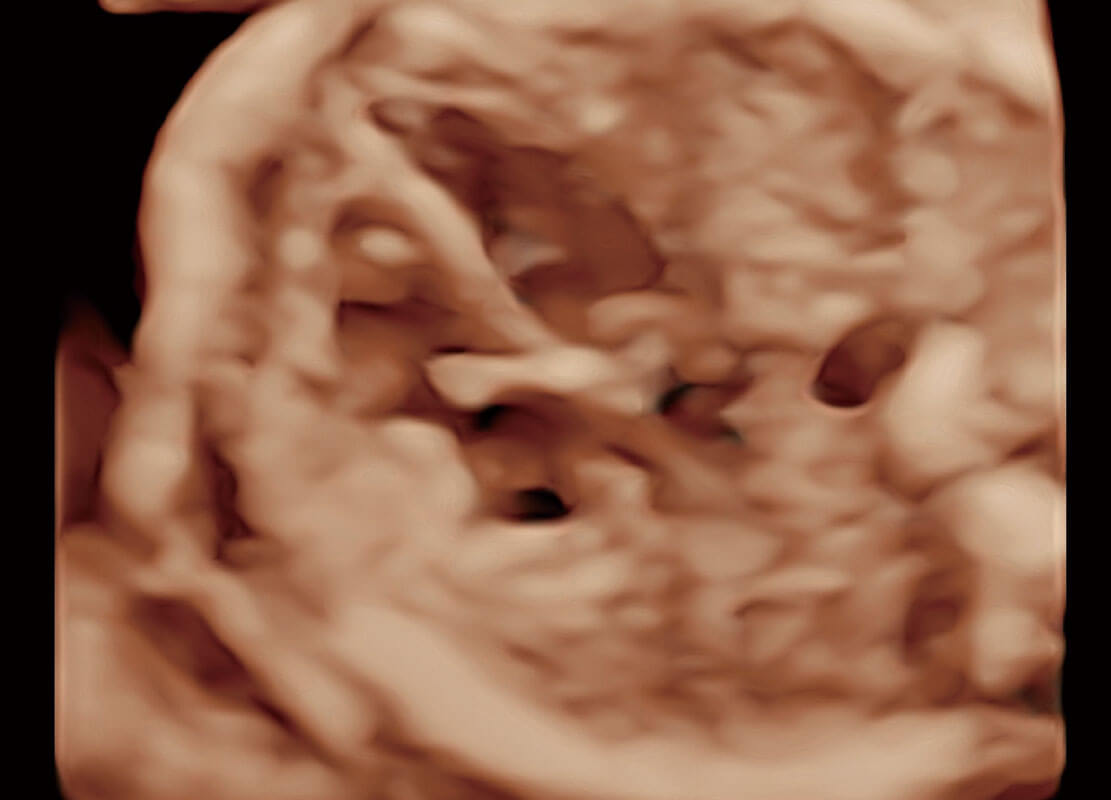

腔内三维-光影成像

高分辨率容积成像-早孕胎儿

光影成像-孕囊